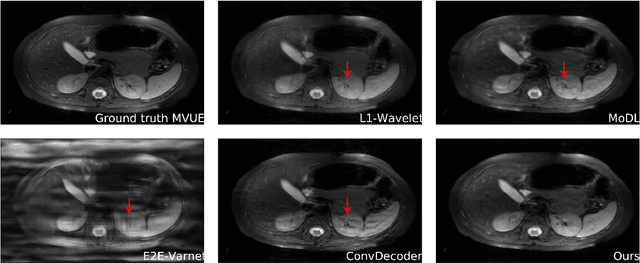

Abstract:The CSGM framework (Bora-Jalal-Price-Dimakis'17) has shown that deep generative priors can be powerful tools for solving inverse problems. However, to date this framework has been empirically successful only on certain datasets (for example, human faces and MNIST digits), and it is known to perform poorly on out-of-distribution samples. In this paper, we present the first successful application of the CSGM framework on clinical MRI data. We train a generative prior on brain scans from the fastMRI dataset, and show that posterior sampling via Langevin dynamics achieves high quality reconstructions. Furthermore, our experiments and theory show that posterior sampling is robust to changes in the ground-truth distribution and measurement process. Our code and models are available at: \url{https://github.com/utcsilab/csgm-mri-langevin}.